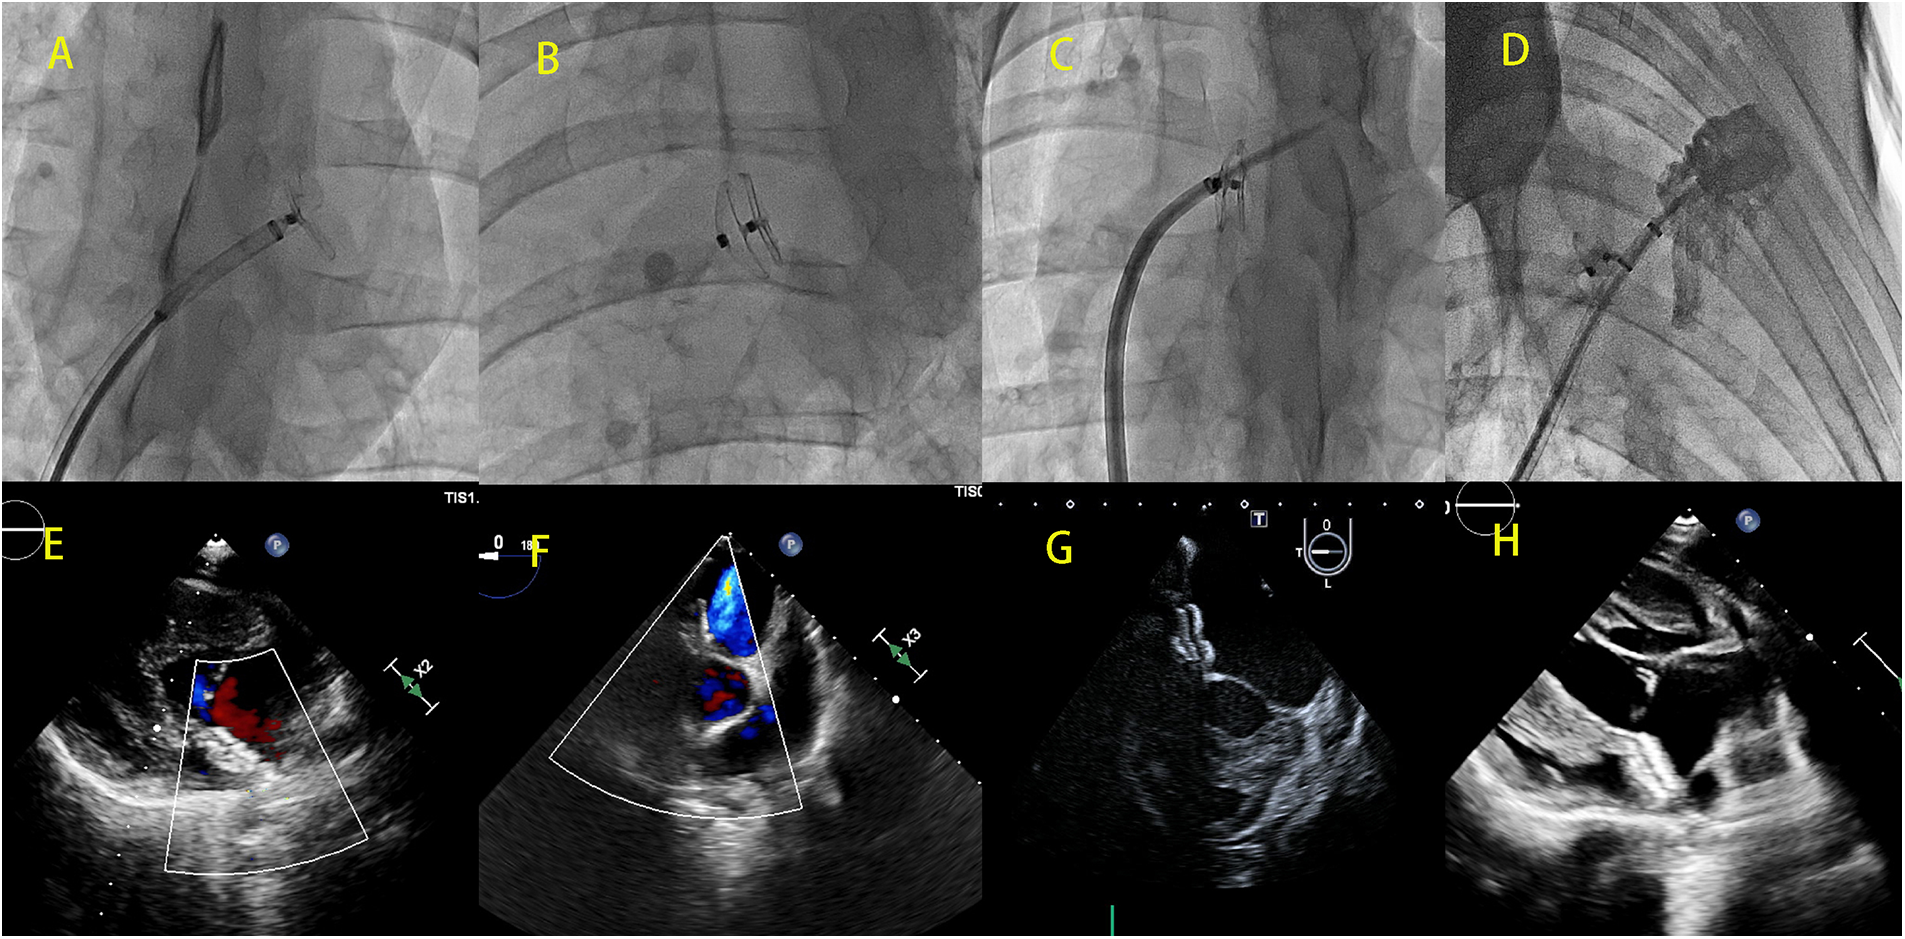

Figure 2

DSA images (A–D) and cardiac ultrasound images (E–H) showing the implantation of a bilateral asymmetric single-rivet PFO occluder device in the reserved interatrial septum puncture area. (A) Left ventricular disc of the deployed occluder device; (B) morphology of the fully deployed occluder device; (C) successful puncture of the interatrial septum through the puncture site reserved by the occluder device after 3 months of initial implantation; (D) left atrial angiography performed through the sheath inserted via the interatrial septum; (E,F) no residual shunting observed immediately after the implantation of the occluder device; (G,H) cardiac ultrasound demonstrating the morphology of the occluder device after implantation.